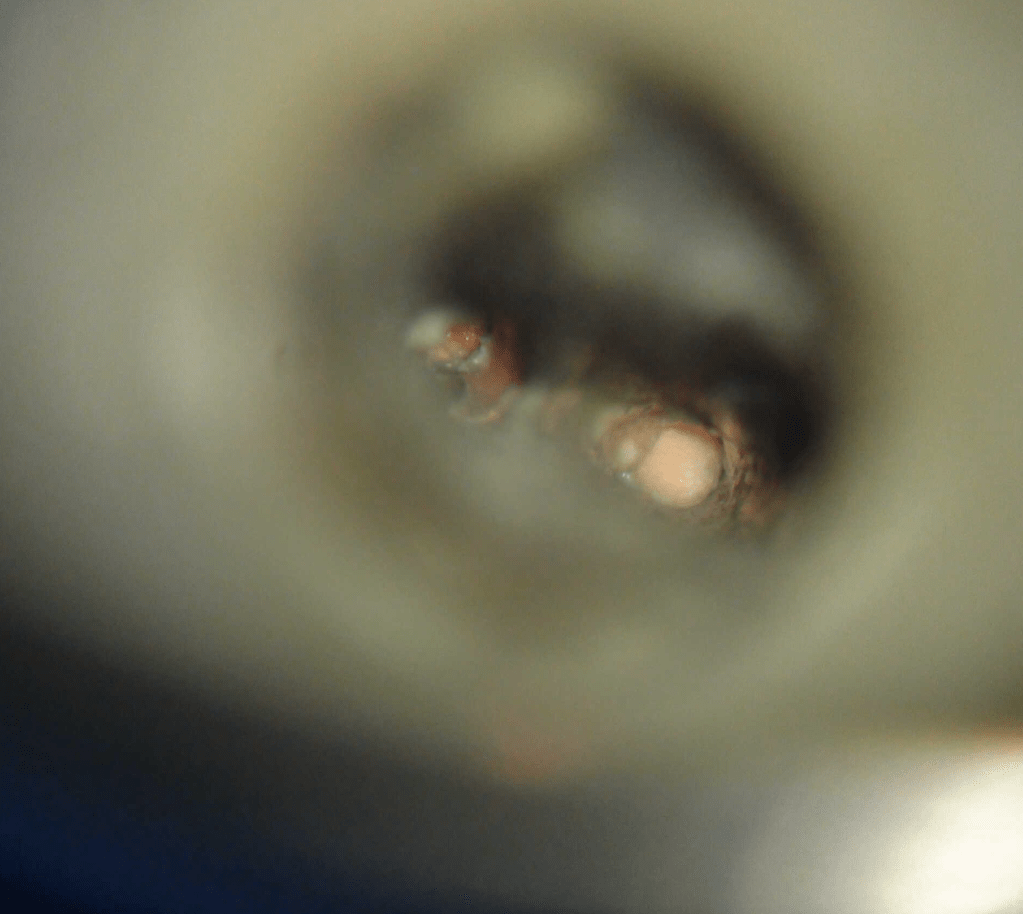

Remoción 2 Postes Moscados